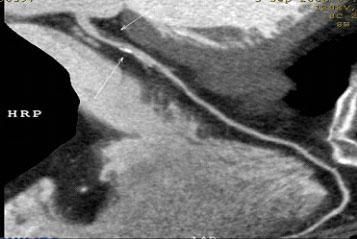

1.冠脈軟斑塊:

2.混合性斑塊:

3.對于斑塊性質的确定,CT優于DSA: